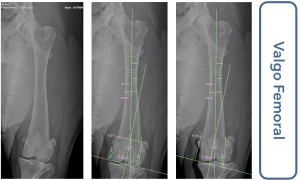

Sou médico veterinário especializado em ortopedia e cirurgias complexas em cães, com atuação em Ribeirão Preto. Realizo procedimentos como cirurgia de ligamento cruzado (TPLO), correção de luxação de patela e tratamento de fraturas, sempre com foco na recuperação funcional e qualidade de vida do paciente.

• Cirurgia de joelho, patela e fraturas em cães

• Atendimento de casos complexos com planejamento cirúrgico preciso